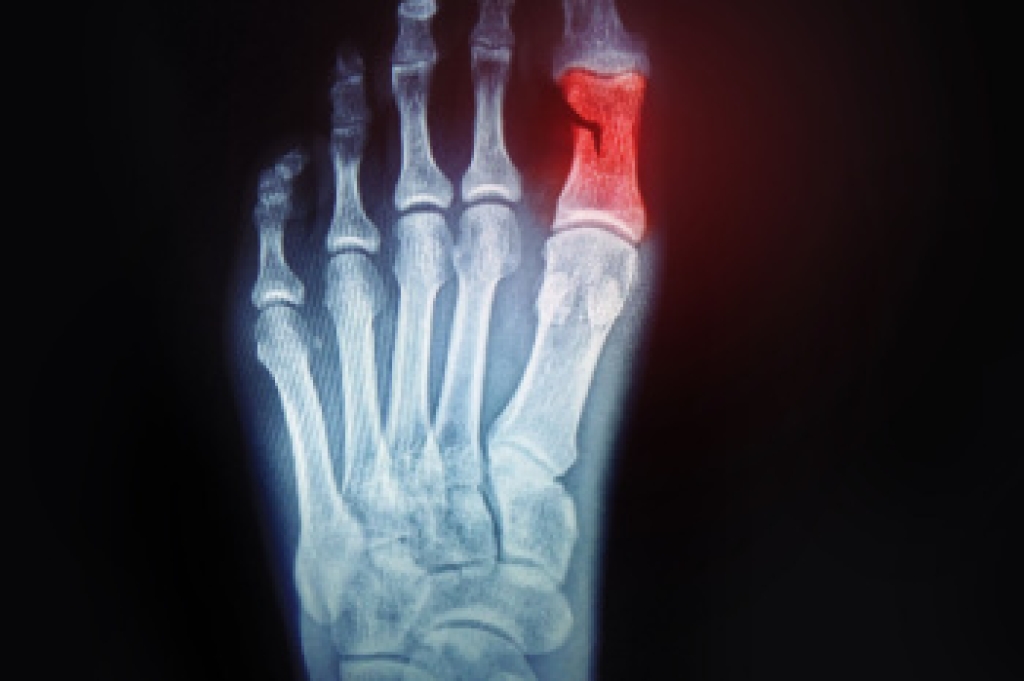

In order to diagnose your bunion, your podiatrist may ask about your medical history, symptoms, and general health. Your doctor might also order an x-ray to take a closer look at your feet. Nonsurgical treatment options include orthotics, padding, icing, changes in footwear, and medication. If nonsurgical treatments don’t alleviate your bunion pain, surgery may be necessary.